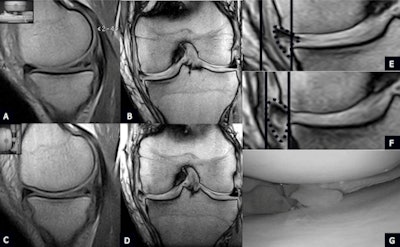

| Unstable degeneration (type 3 lesion) of the medial meniscus. Type 3 degeneration tear of the medial meniscus well-depicted on sagittal PD-W (A) and coronal GE-W (B) scan planes in the supine position. (C) Sagittal scan plane PD-W in the orthostatic position shows fragmentation of the meniscus. (D) Coronal weight-bearing GE-W suggests an unstable lesion well-depicting a lateral shift of the meniscus: See lines in (E) supine and (F) upright. (G) Arthroscopy confirms unstable and fragmented type 3 degenerative tear of the medial meniscus. All images courtesy of Dr. Antonio Barile. |

Barile and his colleagues sought to assess the role of dedicated low-field standard and weight-bearing MRI in the evaluation of stable or unstable tears of medial meniscus in comparison with arthroscopy. They studied knee MRI examinations performed with a 1.5-tesla MRI scanner (Signa Horizon, GE Healthcare) from July 2010 to August 2011, and reported their findings in an article in press published online in the European Journal of Radiology (30 November 2012).

The authors retrospectively reviewed and analyzed 20 MRI exams of normal knees and 57 MRI exams of knees with clinical evidence of tears of the medial meniscus. In the same session, after conventional 1.5-tesla and dedicated 0.25-tesla supine MRI examination, the patients underwent a weight-bearing examination with the same dedicated MRI unit. In all cases, sagittal and coronal proton-density weighting were used. All patients underwent arthroscopy 18 to 25 days after the weight-bearing MRI.

In the first group, no statistically significant anatomical modifications of shape, intensity, and position of the medial meniscus were observed between standard 1.5-tesla, dedicated supine, and upright MRI. In group A, the images acquired in the supine position (dedicated and 1.5-tesla MRI) documented in 21 cases a traumatic tear (group 2A) and in 36 cases a degenerative tear (group 2B).

"After an 82° table rotation, MRI examinations allowed evaluation of the physiological variations of the signal under physiological load, as well as of the medial meniscal position and morphology. Morphology, intrameniscal signal and measurements of the grade of medial meniscal extrusion, evaluated on both sagittal and coronal planes, did not show statistically significant differences," they wrote.

In group 2A, weight-bearing MRI showed the presence of an unstable tear in only 19 out of 36 cases. In group 2B, weight-bearing MRI showed this in only nine out of 21 cases. Arthroscopy confirmed the weight-bearing MRI diagnosis in all cases.